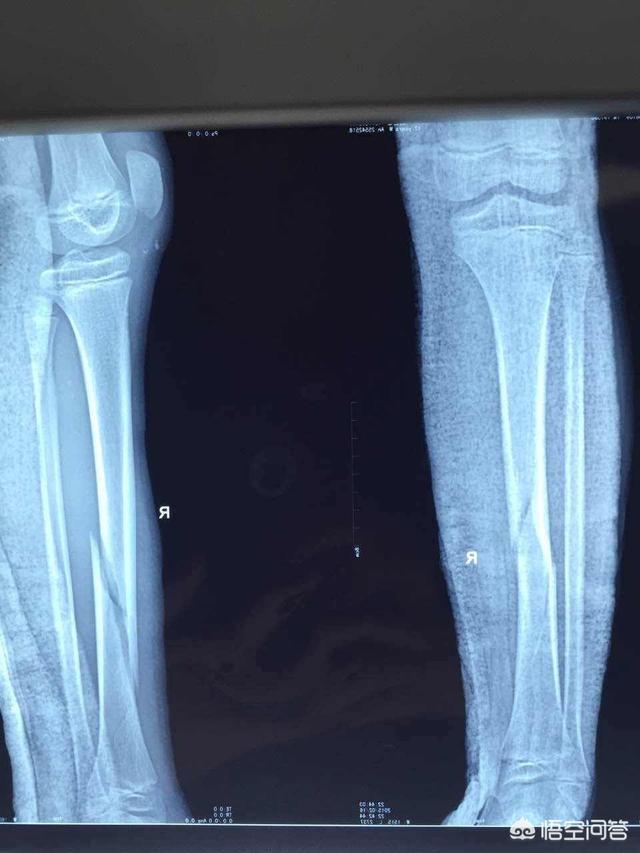

下图就是2型糖尿病引起的下肢胫腓骨干骨折